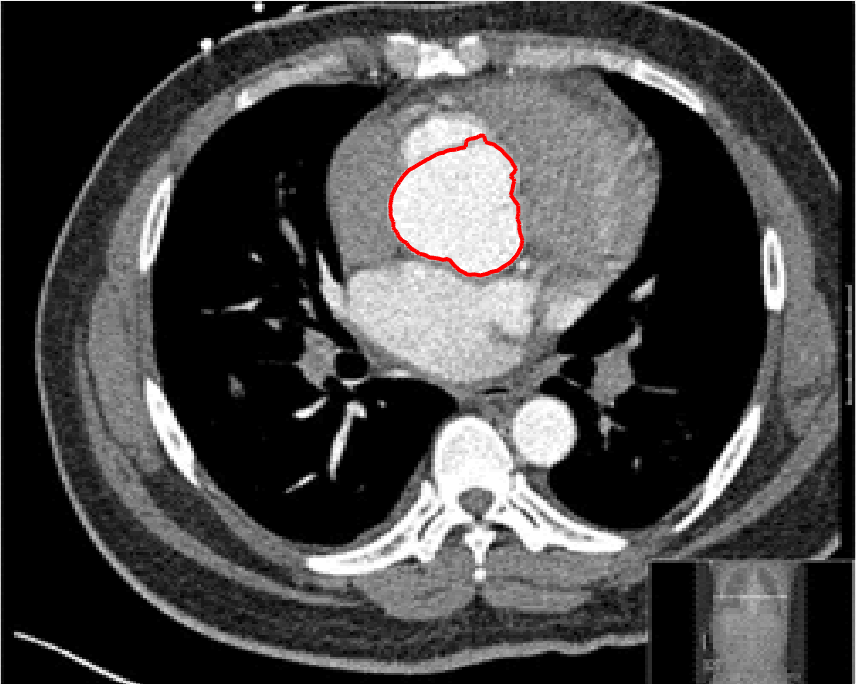

Four sets of test results are shown below. In Test 1 we compare models M1 – M6 to the proposed model M7 for two images which are hard to segment. The first is a CT scan from which we would like to segment the lower portion of the heart, the second is an MRI scan of a knee and we would like to segment the top of the Tibia. See Figure 9 for the test images and the marker sets used in the experiments. In Test 2 we will review the sensitivity of the proposed model to the main parameters. In Test 3 we will give several results achieved by the model using marker and anti-marker sets. In Test 4 we show the initialisation independence and marker independence of the Geodesic Model on real images.

Test 1 – Comparison of models M1 – M7.

In this test we give the segmentation results for models M1 – M7 for the two challenging test images shown in Figure 9. The marker and anti-marker sets used in the experiments are also shown in this figure. After extensive parameter tuning, the best final segmentation results for each of the models are shown in Figures 10 and 11. For M1 – M4 we obtain incorrect segmentations in both cases. In particular, the results of M2 and M4 are interesting as the former gives poor results for both images, and the latter gives a reasonable result for Test Image 1 and a poor result for Test Image 2. In the case of M2, the regularisation term includes the edge detector and the distance penalty term (see (4)). It is precisely this which permits the poor result in Figures 10(b) and 11(b) as the edge detector is zero along the contour and the fitting terms are satisfied there (both intensity and area constraints) – the distance term is not large enough to counteract the effect of these. In the case of M4, the distance term and edge detector are separated from the regulariser and are used to weight the Chan-Vese fitting terms (see (9)). The poor segmentation in Figure 11(b) is due to the Chan-Vese terms encouraging segmentation of bright objects (in this case), weighting ω𝜔\omega enforces these terms at all edges in the image and near \mathcal{M}. In experiments, we find that M4 performs well when the object to segment is of approximately the highest or lowest intensity in the image, however when this is not the case, results tend to be poor. We see that, in both cases, models M5 and M6 give much improved results to M2 and M4 (obtained by incorporating the geodesic distance penalty into each). The proposed Geodesic Model M7 gives an accurate segmentation in both cases. It remains to compare M5, M6 and M7. We see that M5 is a non-convex model (and cannot be made convex [39]), therefore results are initialisation dependent. It also requires one more parameter than M6 and M7, and an accurate set \mathcal{M} to give a reasonable area constraint in (4). These limitations lead us to conclude M6 and M7 are better choices than M5. In the case of M6, it has the same number of parameters as M7 and gives good results. M6 can be viewed as the model M7 with weighted intensity fitting terms (compare (18) and (30)). Experimentally, we find that the same quality of segmentation result can be achieved with both models generally, however M6 is more parameter sensitive than M7. This can be seen in the parameter map in Figure 12 with M7 giving an accurate result for a wider range of parameters than M6. To show the improvement of M7 over previous models, we also give an image in Figure 13 which can be accurately segmented with M7 but the correct result is never achieved with M6 (or M3). Therefore we find that M7 outperforms all other models tested M1 – M6.

Refer to captionRefer to captionRefer to captionRefer to caption

(i)                                 (ii)                                 (iii)                                 (iv)

Figure 9: Test 1 setting: (i) Image 1;  (ii) Image 1 with marker and anti-marker set shown in green and pink respectively;  (iii) Test Image 2; (iv) Image 2 with marker set shown.

Refer to caption

(a) M1 (Left to right:) Test Image 1 with markers (red) and anti-markers (blue), foreground segmentation and background segmentation (we used published software, no parameter choice required).

(b) M2 λ=1𝜆1\lambda=1, γ=10𝛾10\gamma=10.

(c) M3 λ=5𝜆5\lambda=5, θ=3𝜃3\theta=3.

(d) M4 λ=1/4𝜆14\lambda=1/4.

(e) M5 λ=5,γ=3,θ=110formulae-sequence𝜆5formulae-sequence𝛾3𝜃110\lambda=5,\gamma=3,\theta=\frac{1}{10}.

(f) M6 λ=15,θ=3formulae-sequence𝜆15𝜃3\lambda=15,\theta=3.

(g) M7 λ=10,θ=1formulae-sequence𝜆10𝜃1\lambda=10,\theta=1.

Figure 10: Visual comparison of M1 – M7 results for Test Image 1. M1 segmented part of the object, M2 – M4 failed to segment the object, M5 gave a reasonable result (though not accurate) and, M6 and M7 correctly segmented the object.